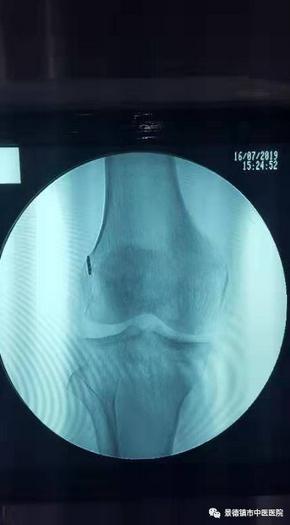

前交叉重建術(shù)后